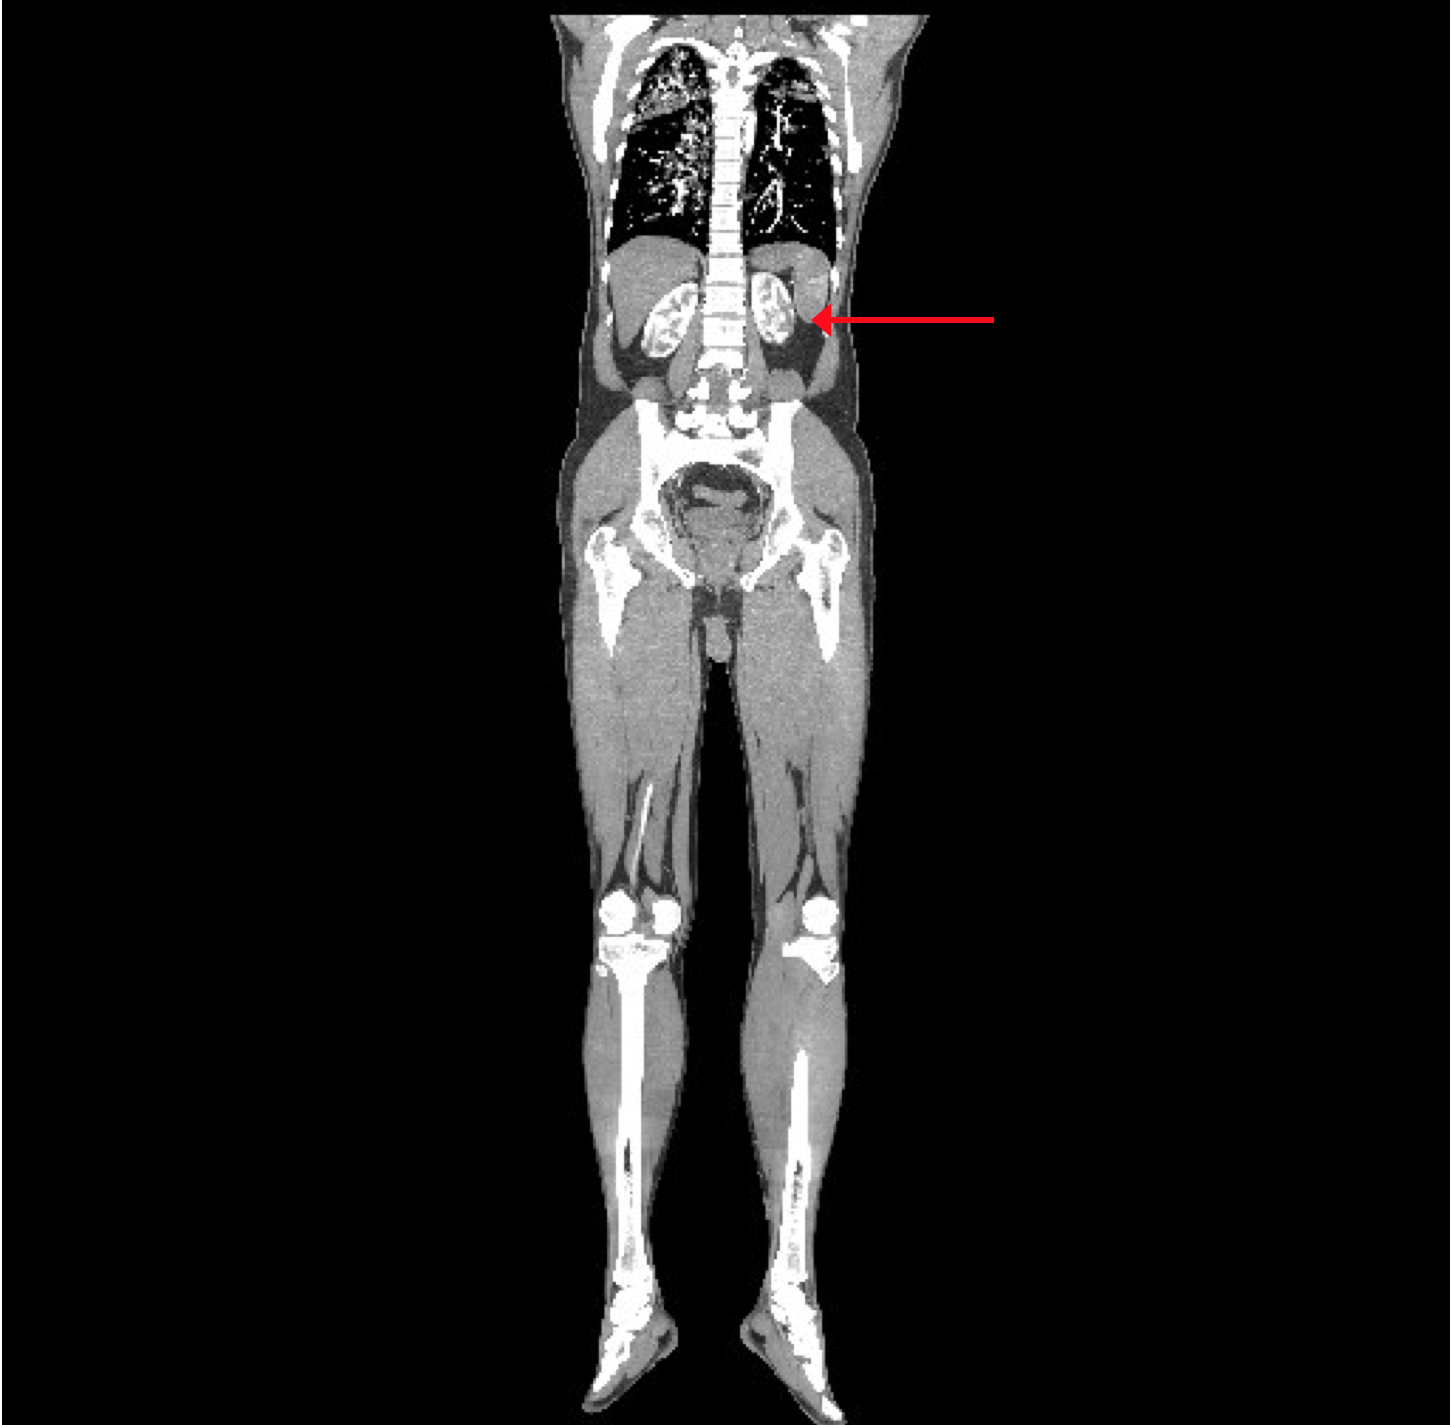

The CT angiogram and CT chest aortogram revealed a hypodense filling defect in the aorta below the level of the renal arteries causing partial occlusion of the aorta (Figure 2). There was complete occlusion of the left common iliac artery just after bifurcation of aorta extending up to the common femoral artery (Figure 3). There was good contrast uptake in right common iliac artery, femoral artery, superficial femoral artery up to the popliteal artery then the abrupt cut off of right popliteal artery present with no contrast filling seen in the distal arteries (Figure 4 and 5). Additionally, multiple bilateral wedge shaped infarcts seen in both the kidneys and the spleen (Figures 6). Chest x-ray was normal.

Figure 5: CT Aortogram revealing multiple infarcts in the both kidneys in coronal section.